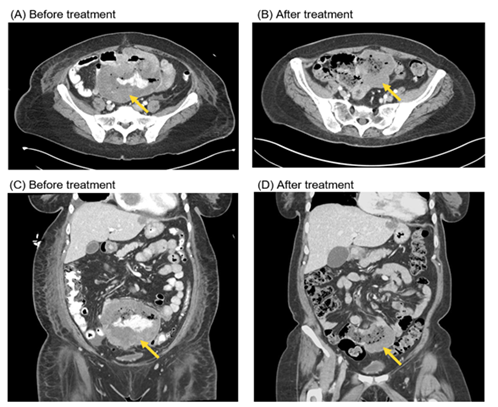

A 62-year-old Caucasian woman was admitted to the hospital with three months of worsened dyspneaon exertion, fatigue and unintentional weight loss of ten pounds. Labs showed iron deficiency anemia with hemoglobin down trended to 6.4g/dL and positive fecal occult blood test, normal CEA (1.5ng/mL) and CA 19-9 (7U/mL), with elevated LDH (541IU/L).CT scan of the chest, abdomen and pelvis revealed two non-obstructing small bowel masses(5.3cm jejunal mass and 12.3cm ileal mass), hypoattenuated right hepatic lesions, sub-centimeter right pulmonary nodules (up to 9mm), and a 3cm by 3cm by 4cm intracardiac mass at the tricuspid annulus(Figures 1A, 1C, 2A). MR of the liver revealed three right hepatic lobe lesions, measuring up to 1.3cm. Transthoracic echocardiogram confirmed the large mobile right atrial mass attaching below the anterior tricuspid valve leaflet and protruding into the right ventricle (Figure 3). Subsequent cardiac MRI characterized the right atrial mass as a mixture of tumor and thrombus. MRI brain revealed small subacute infarct in the left cerebellar hemisphere, but no intracranial metastasis.

Figure 1 Computed tomography scans of the abdomen/pelvis demonstrate treatment response to immunotherapy with 4 cycles of ipilimumab/nivolumab followed by maintenance PD-1 inhibition. The arrows point to the large ileal melanoma lesion, at time of diagnosis (A, C) and at 6 months after (B, D).

Dual checkpoint blockade with ipilimumab (3mg/kg) and nivolumab (1mg/kg) given intravenously was started on hospital day 18 with good tolerance. The patient was discharged after 40 days of hospitalization, with continued requirement for intermittent blood transfusions. Molecular testing was confirmed and expanded on via FoundationOne analysis of the original tissue biopsy, revealing tumor mutational burden of 14 mutations/Mb, homozygous loss of CDKN2A and CDKN2B, and TP53 1245S in addition to NRAS Q61R and MSI stable status. She proceeded to complete four cycles of ipilimumab/nivolumab dosed every three weeks, followed by maintenance PD-1 inhibitor, and improved clinically with less frequent blood transfusion requirement. At six months since diagnosis, updated scans and echocardiogram continued to show treatment response with stable to reduced sizes of the cardiac and mesenteric masses (Figure 1B, 1D, 2B).